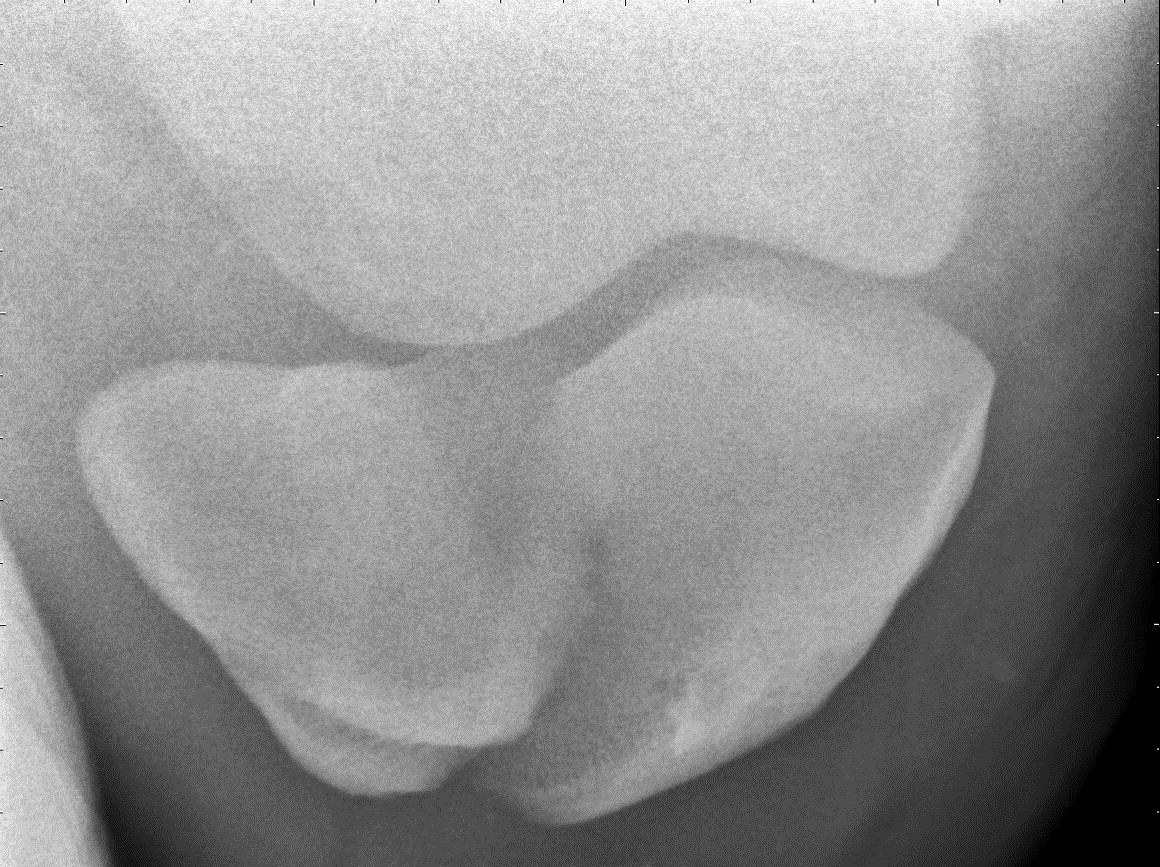

Image Comminuted fracture of second phalanx fracture, horse MSD Hip Fracture In Horses New insights into how bone forms, adapts and heals are revolutionising prevention and repair of bone fractures in horses, explains patrick pollock frcvs. A horse may fracture its pelvis at any age, but the injury is most common in horses 6 months to 2 years old. Fracture of the dorsal acetabular rim may accompany the dislocation. Horses that slip or. Hip Fracture In Horses.